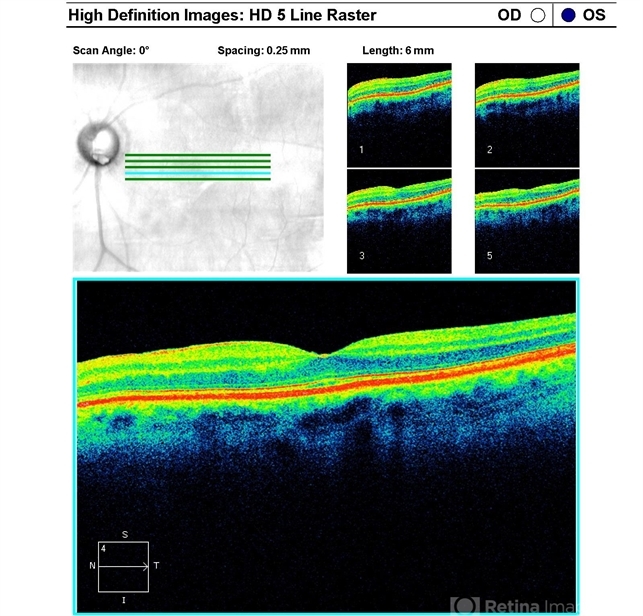

Optical coherence tomography system

Zeiss Cirrus - Description

- Left macular OCT of a 77-year-old woman with bilateral optic nerve pits and glaucoma, stable over 20 years.